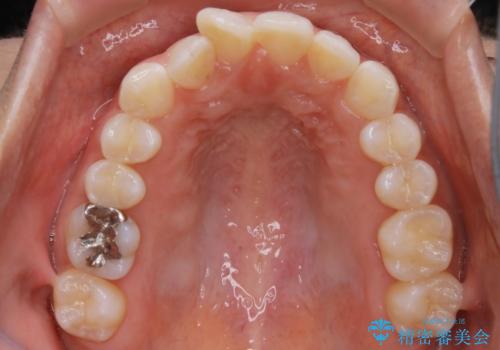

【非抜歯】下の前歯が1本少ない場合の矯正治療

- 前歯のガタつきを主訴に来院されました。

生まれつき下の前歯が1本少なく、その分のスペースを上の前歯がガタつくことで埋めているという状況でした。

上下それぞれのガタつきをとっていく過程で、歯1本分のスペースの差を、上顎の前歯のIPRで調整して並べる方法をご提案させていただきました。